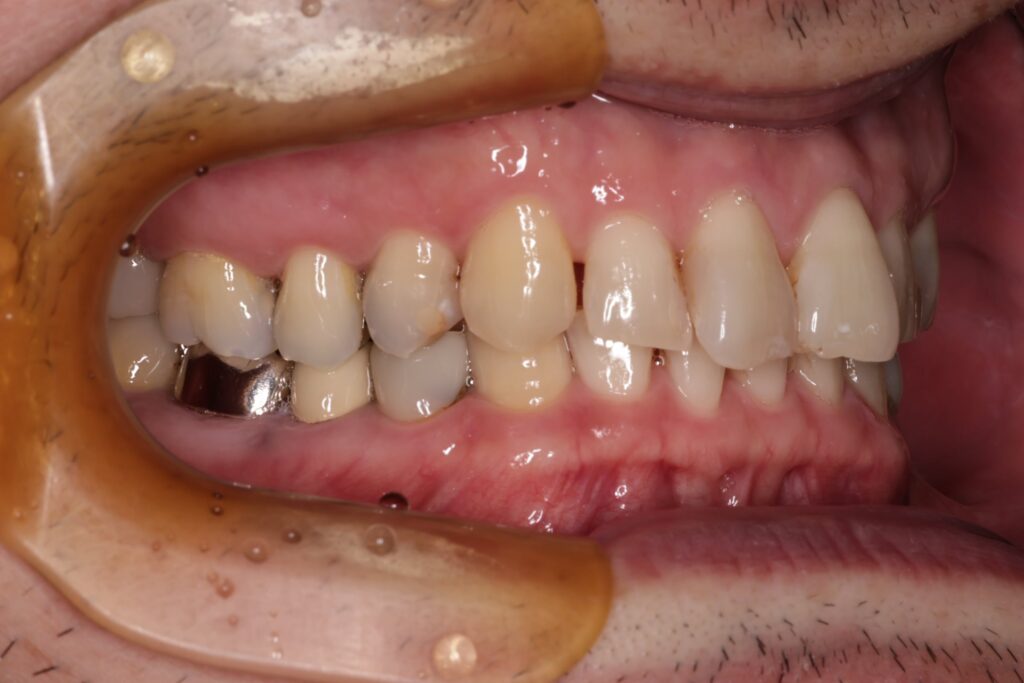

初診時の口腔内の状態:

口腔内には多数の銀歯(銀合金)が確認されました。患者様は過去に多くの虫歯治療を受けており、そのほとんどが保険適用内の銀合金で修復されていました。

Before